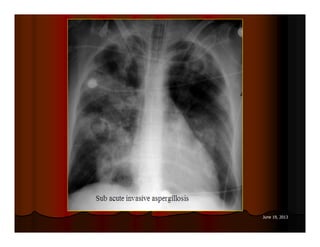

NHÖÕNG BOÙNG DAÏNG HANG

ASPERGILLOME

77 June 19, 2013

DẤU HIỆU LỤC LẠC

(SIGN OF TINTINNABULUM)

Sign of tintinnabulum = Signe de grelot.

Nấm Aspergillus có thể gây bệnh ở người với 2 thể chính:

Thể xâm lấn mạch máu (Angioinvasive Aspergillosis): tổn

thương lan toả, gặp ở người có cơ địa suy giảm miễn dịch. Ở

thể này ta có dấu hiệu vầng hào quang (halo sign) trên CT.

Thể banh nấm (Saprophytic Aspergillosis = Aspergilloma):

hình thành banh nấm (fungus ball) trong lòng các tổn thương

hang ở phổi, thường gặp ở BN có hang lao. Thể này cho dấu

hiệu lục lạc (Tintinnabulum sign) hay dấu hiệu liềm khí (Air

crescent sign) tuỳ theo tác giả.